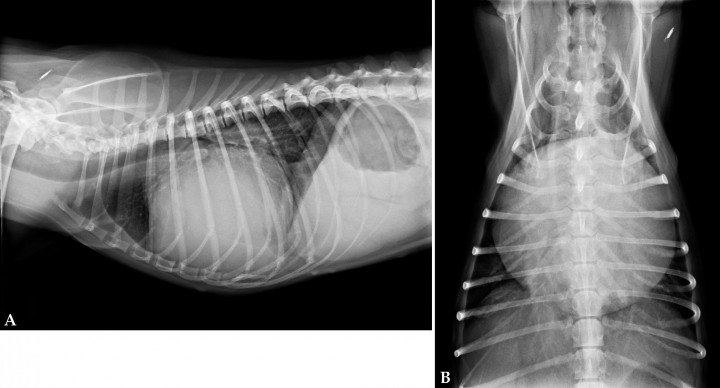

Radiografía de tórax

Para valorar las modificaciones cardiacas (aumento AI, VI, cardiomegalia gradual) y la presencia de signos de congestión cardiopulmonar.

Radiografía de tórax

DX de fallo cardiaco congestivo, por patrón alveolar de edema pulmonar y congestión venosa. Permite evaluar tamaño y forma del corazón